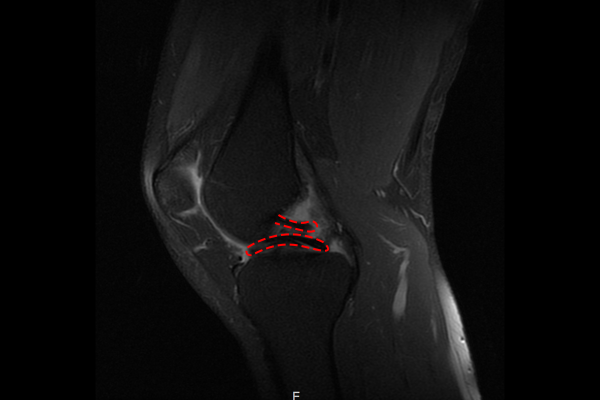

측면 MRI를 보시면 마치 후방십자인대가 2개인 것 같은 double-PCL sign이 확인되는데, 이는 내측 반달연골이 양동이 손잡이 같이 반이 잘리면서 들린 것으로, 양동이 손잡이형 파열(bucket-handle tear)의 특징이기 때문에 무릎 반월상 연골판 양동이 손잡이형 파열(Medial menisucs bucket-handle tear knee Rt)을 진단하였습니다.